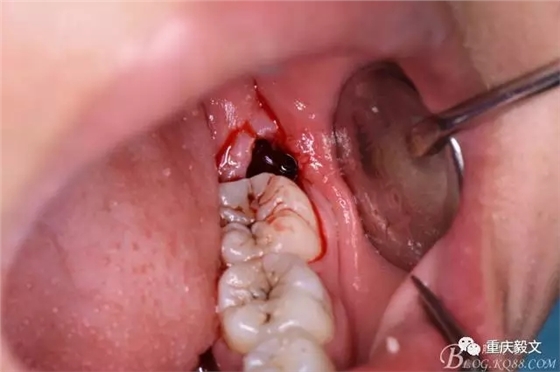

圖9.再把38牙冠近遠(yuǎn)中縱斷

圖10.用丁字挺取出牙冠舌側(cè)部分

圖11.取出的38舌側(cè)部分